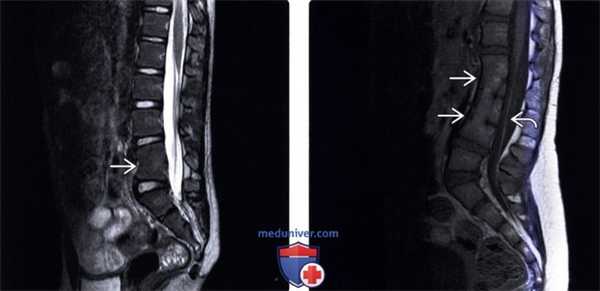

(Слева) Т2-ВИ, сагиттальная проекция: случай нарушения сегментации L4 и L5 позвонков, сопровождающейся патологическим сглаживанием поясничного лордоза и легко выраженной локальной кифотической деформацией на уровне измененного сегмента. Остальные поясничные позвонки выглядят нормально.

(Справа) Т1-ВИ, сагиттальная проекция: случай врожденного нарушения сегментации L1-L4 сегментов. На этих уровнях видны рудиментарные остатки межпозвонковых дисков, отмечается патологическая кифотическая установка позвоночника. Спинной мозг оканчивается на уровне L1-L2, однако фиксирован в спинномозговом канале утолщенной и инфильтрированной жиром терминальной нитью.